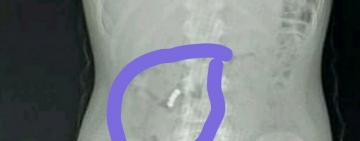

В Одесской области ребенок наглотался магнитов: нужна ваша помощь

Четвероклассник из Черноморской ООШ №2 умудрился съесть сразу четыре небольших ...